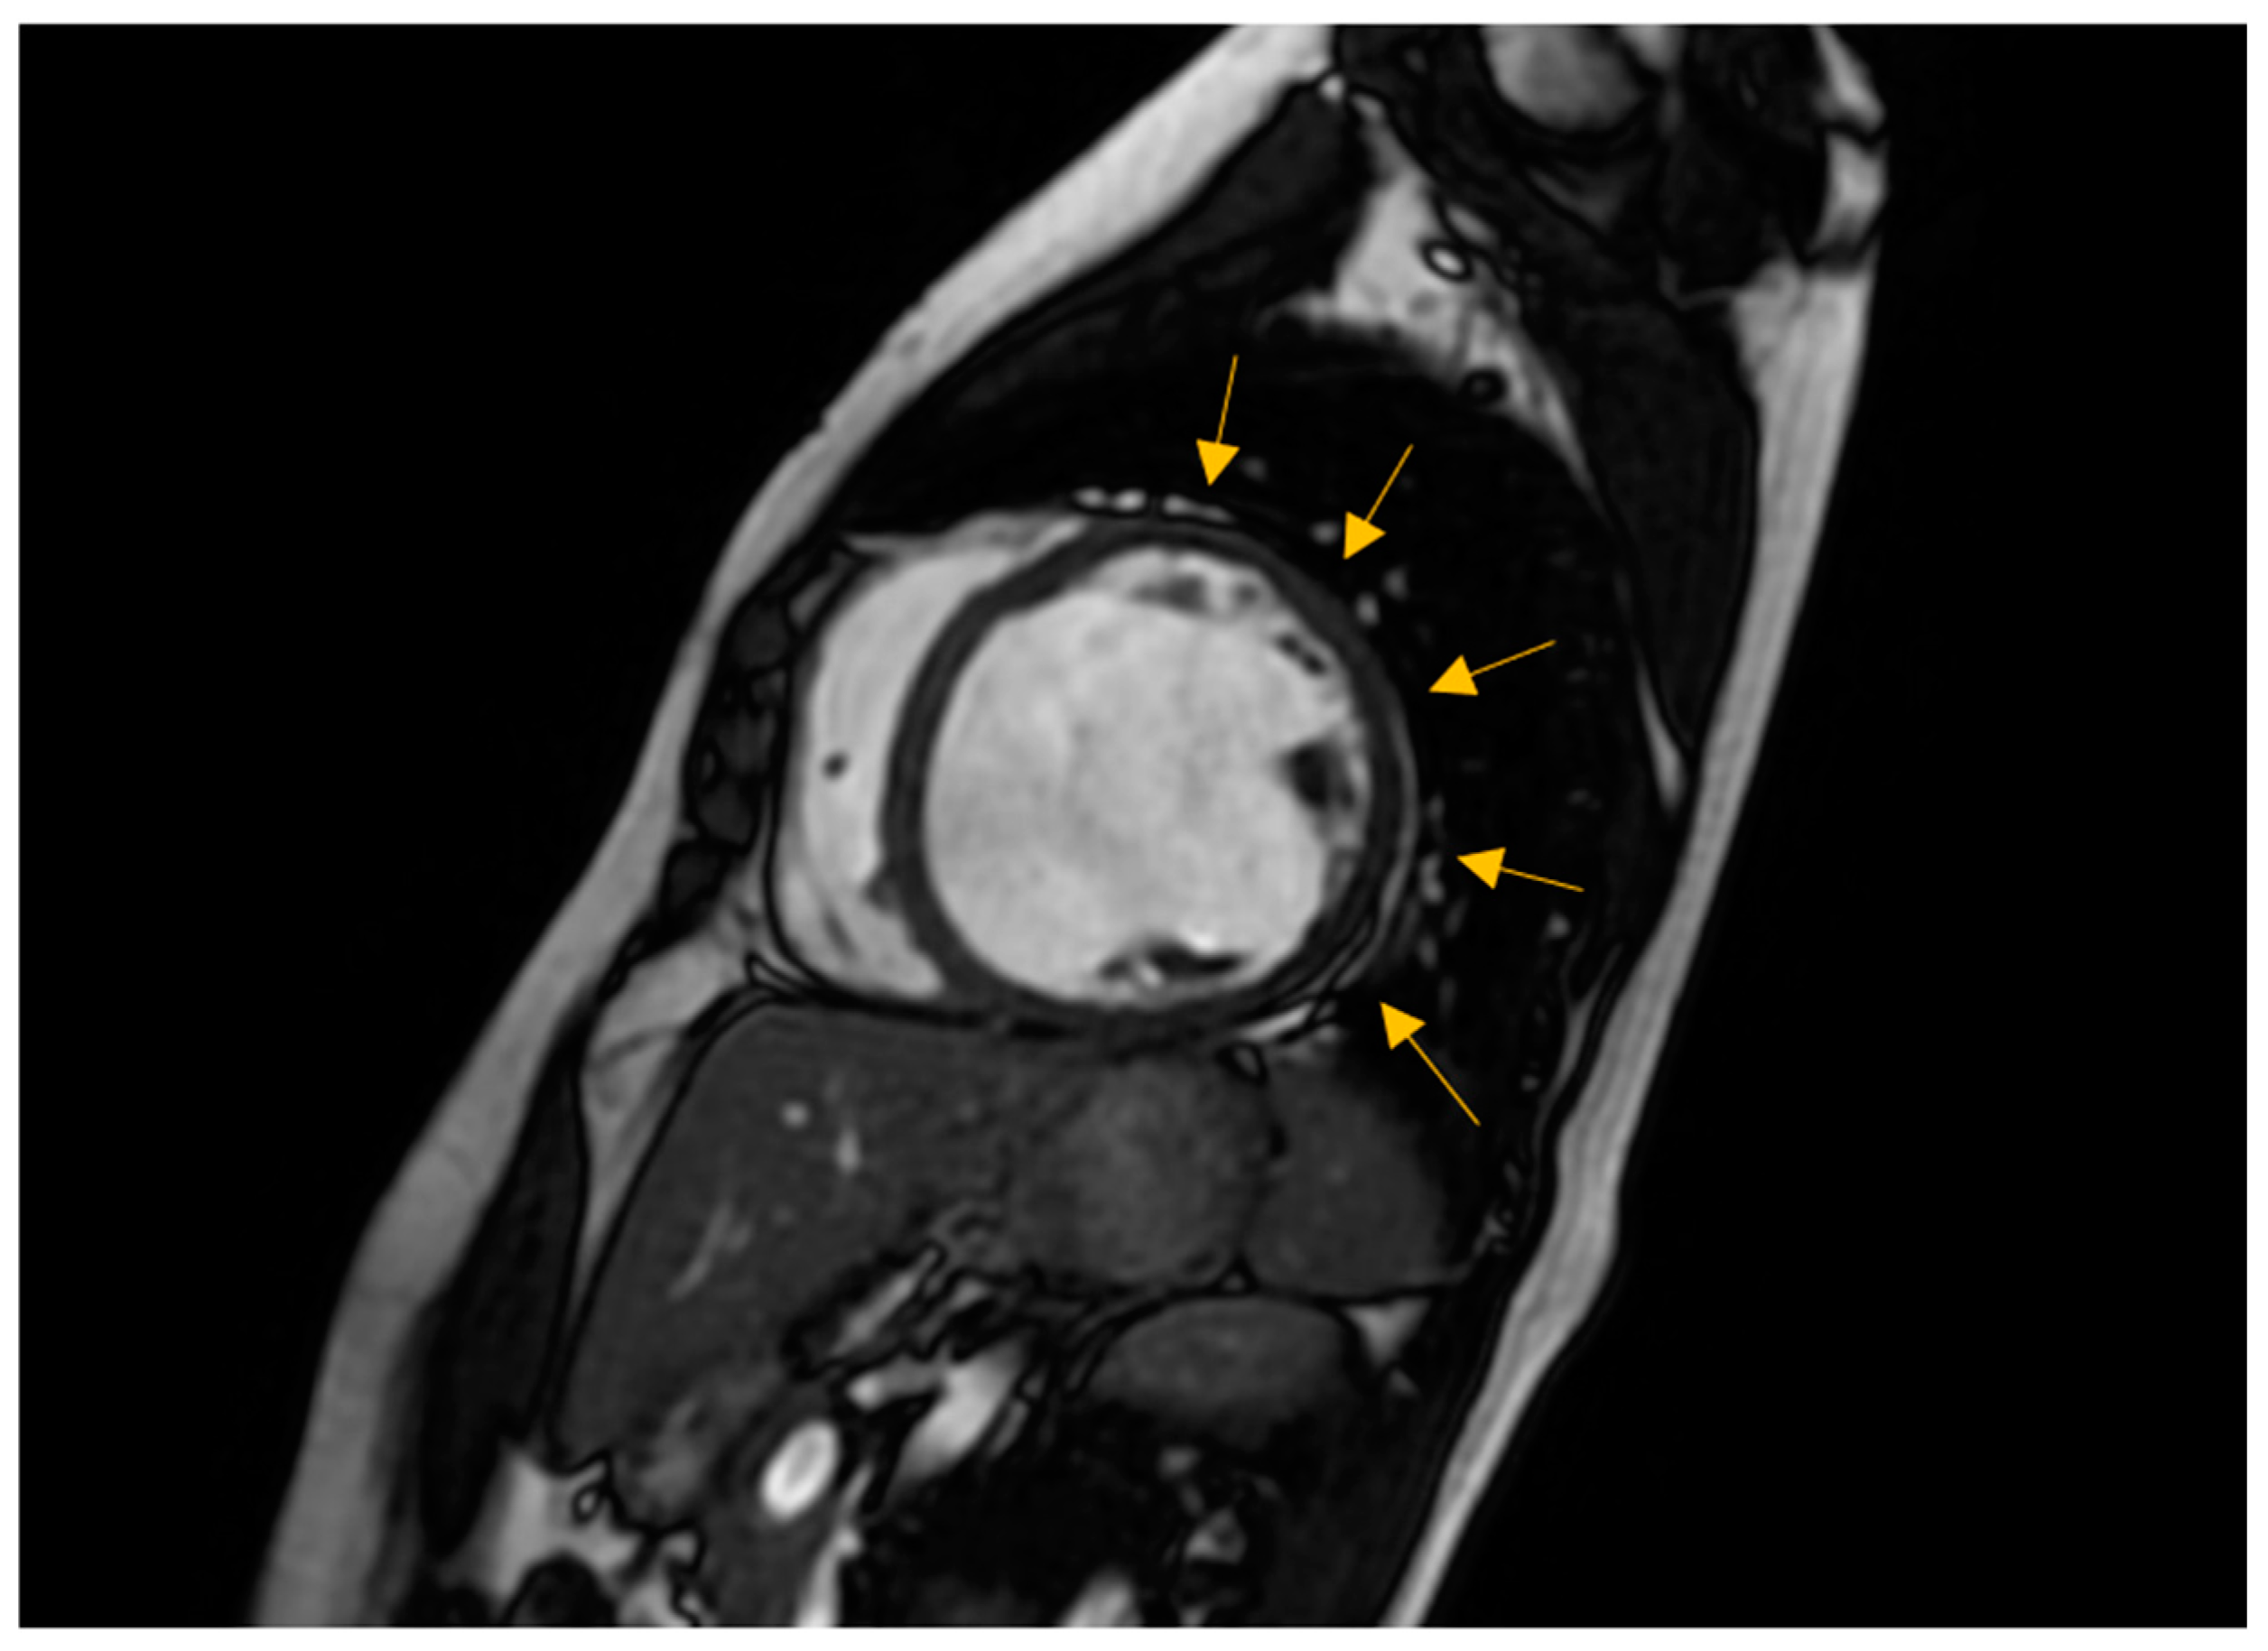

3.2. Non-Invasive Imaging Methods